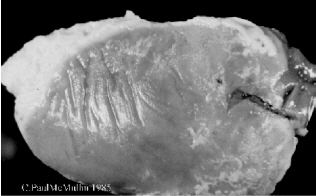

- Perihepatitis.

| Figure 17. Severe perihepatitis in colibacillosis in a broiler parent chicken. The liver is almost entirely covered by a substantial layer of fibrin and pus. |